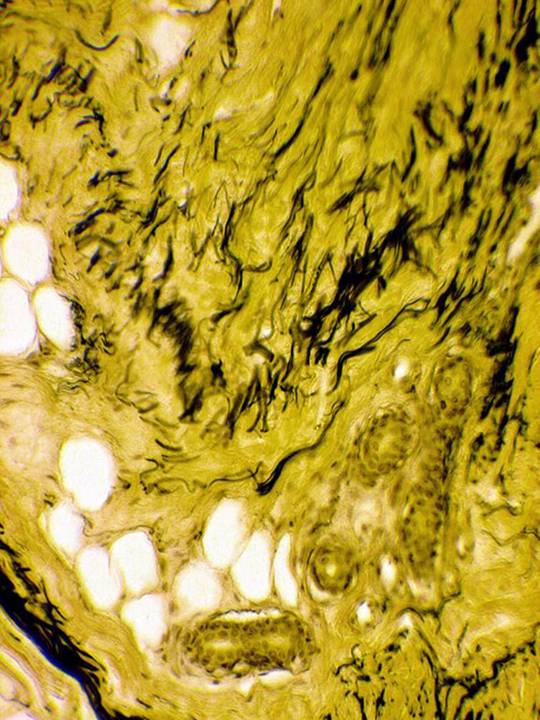

плот соед сетчатого слоя кожи

Плотная волокнистая соединительная ткань сетчатого слоя кожи